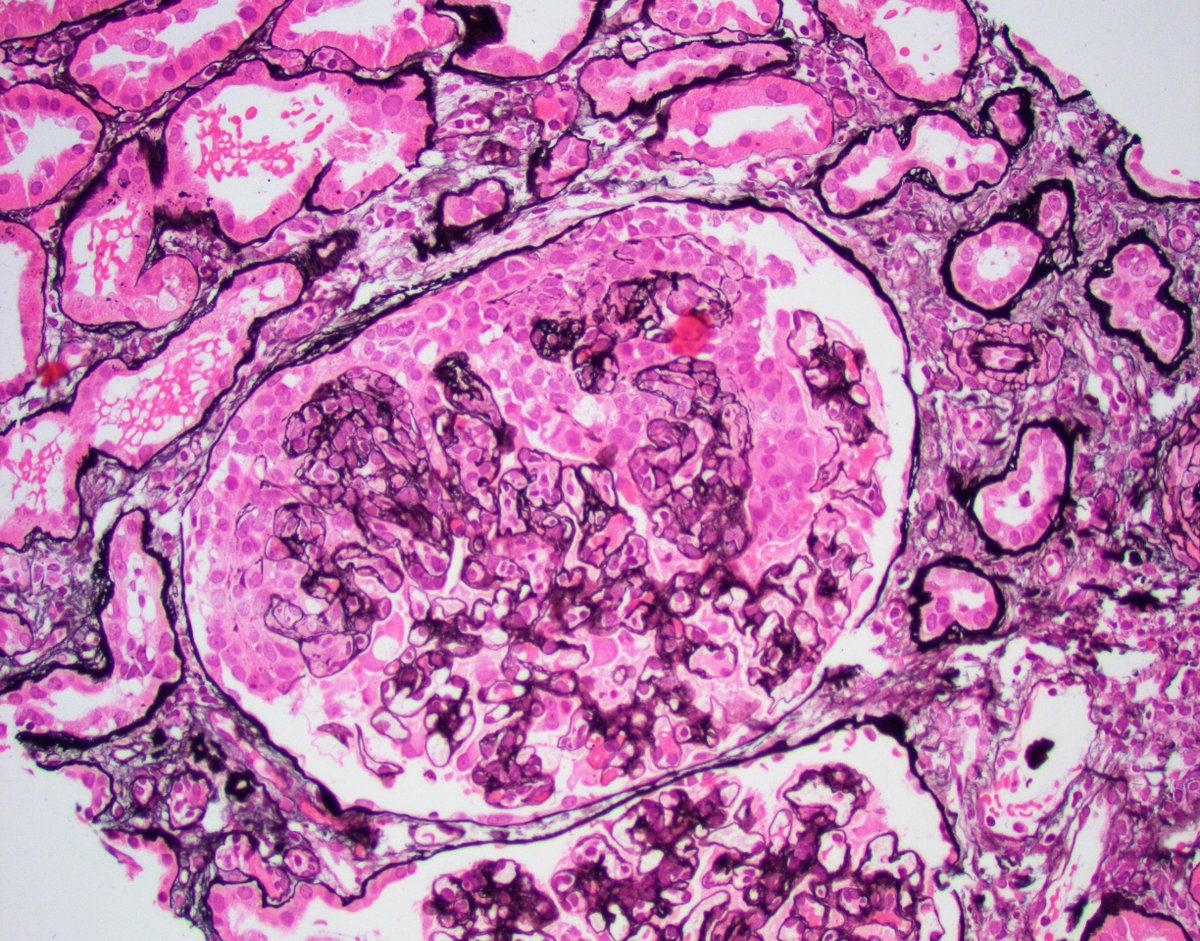

Florid infection related GN. Middle age IV drug user with AKI, hematuria, and heavy proteinuria. Bx with diffuse exudative GN, focal crescents, and many hump like deposits on LM, IF (C3 is picture), and EM. #renalpath #nephropath